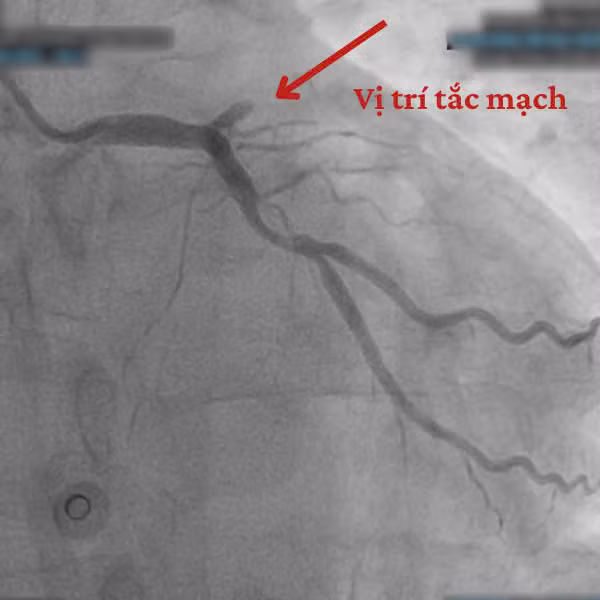

Ngay sau khi ổn định các chỉ số sinh tồn, người bệnh được đưa vào phòng Can thiệp Tim mạch. Qua hình ảnh chụp mạch vành, các bác sĩ phát hiện tắc hoàn toàn ngay sau lỗ động mạch liên thất trước (mạch máu chính nuôi tim).

![]() |

| Hình ảnh trên thiết bị can thiệp |